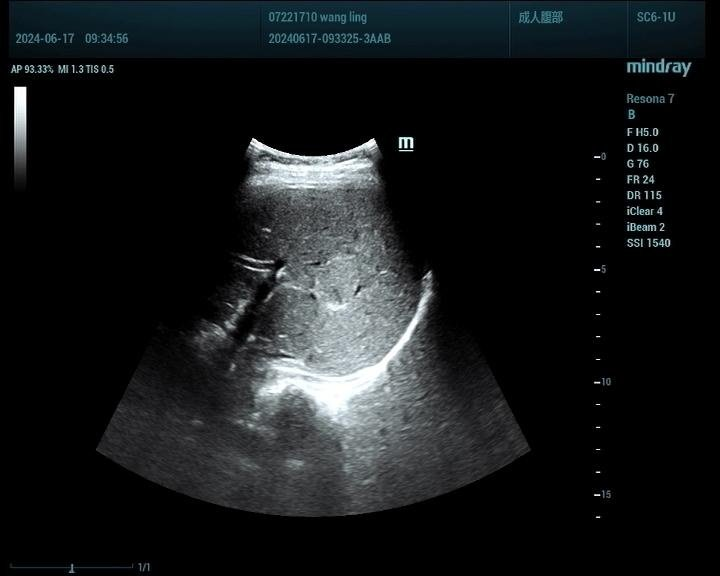

肝脏肿瘤分为良性和恶性,其中血管瘤是最常见的肝脏良性肿瘤,肝癌是最常见的恶性肿瘤。肝脏肿瘤超声影像诊断方面主要有肿瘤病灶的检出、对已检测肿瘤的定性诊断、肝局灶性病灶中肿瘤与非肿瘤病变的鉴别。超声造影对肝脏肿瘤的鉴别诊断主要是通过增强和动态增强方式观察肿瘤。

肝癌病例2